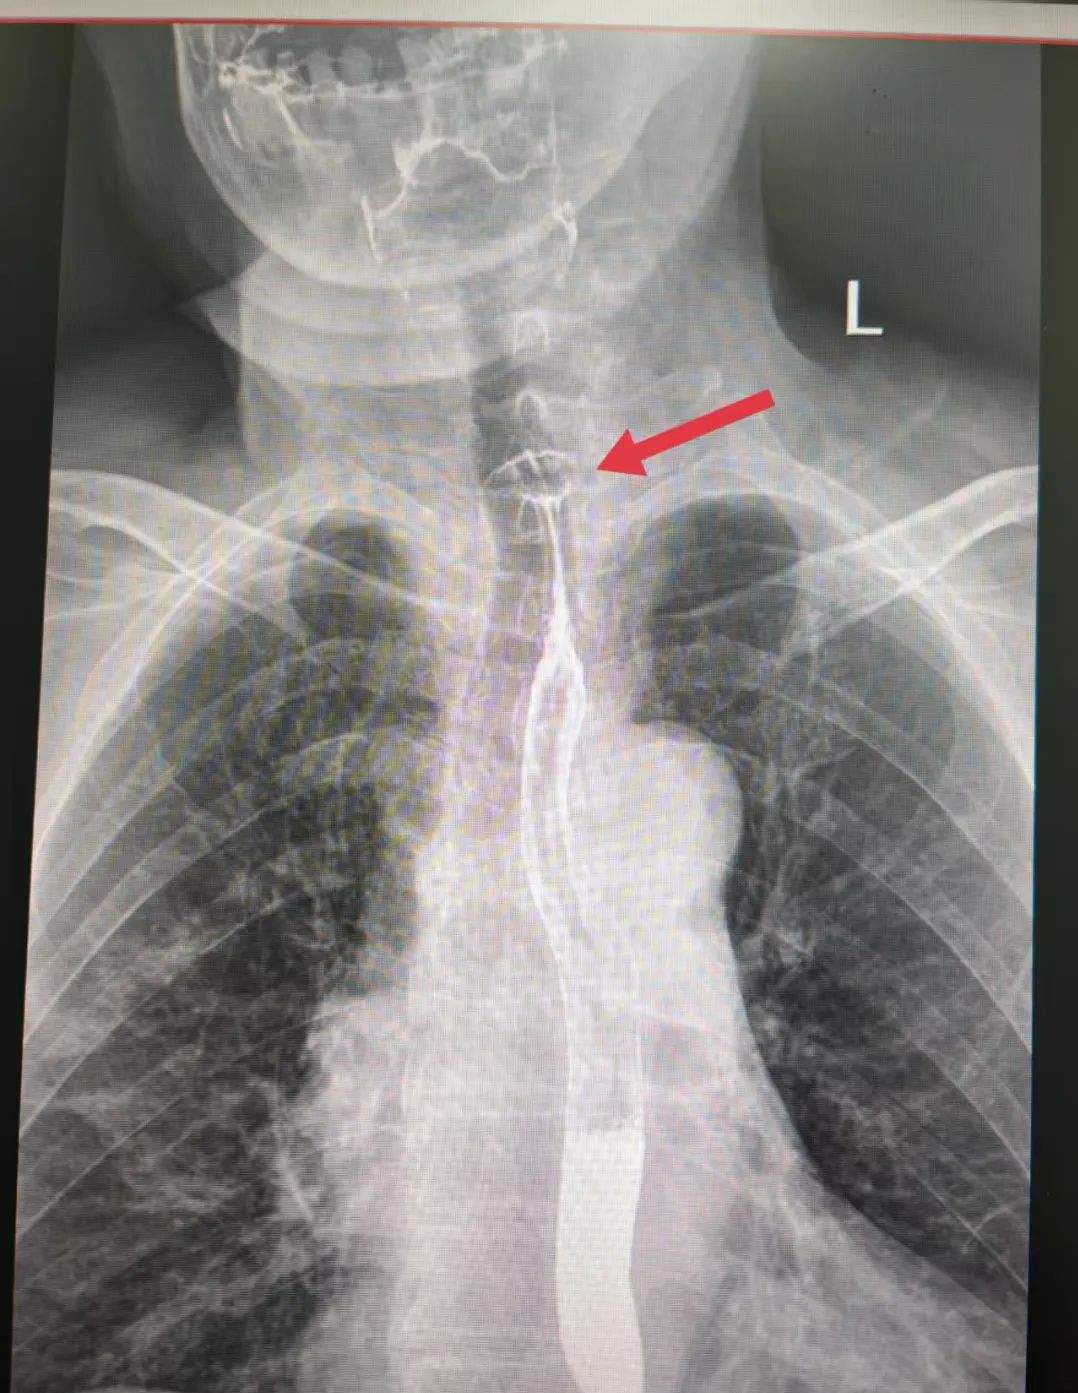

案例一:枣核卡喉 手术脱险

5月28日,陕西榆林75岁的高奶奶食用红枣粽时不慎吞下枣核,顿感咽喉不适、吞咽梗阻,紧急前往医院就诊。检查发现食管上段有异物,高奶奶被收治入院,经手术顺利脱险。